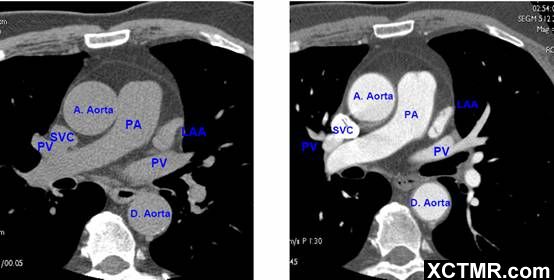

常用英文名称及缩写 LA - Left Atrium 左心房 RA - Right Atrium 右心房 LV - Left Ventricle 左心室 RV - Right Ventricle 右心室 Mitral Valve 二尖瓣 A. Aorta-Ascending Aorta 升主动脉 D. Aorta-Descending Aorta 降主动脉 SVC – Superior Vena Cava 上腔静脉 IVC – Inferior Vena Cava 下腔静脉 PA - Pulmonary Artery 肺动脉 PV - Pulmonary Vein 肺静脉 LMA - Left Main Artery 冠状动脉左主干 LAD - Left Anterior Descending Artery 左前降支 LCX - Left Circumflex Artery 左回旋支 LMB - Left Obtuse Marginal Branch 左边缘支(钝缘支) RCA - Right Coronary Artery 右冠状动脉 PDA - Posterior Descending Artery 后降支 Conus Branch 右动脉圆锥支 LAA – Left Atrial Appendage 左心耳 RAA – Right Atrial Appendage 右心耳 CS - Coronary Sinus 冠状窦 MCV – Middle Cardiac Vein 心中静脉 GCV –Great Cardiac Vein 心大静脉 PIVV – Posterior Intraventricular Vein 后室间静脉(心中静脉) PLVV – Posterior Left Ventricular Vein 左室后静脉 PLV – Posterior Lateral Vein 左室后侧静脉(边缘静脉) | |